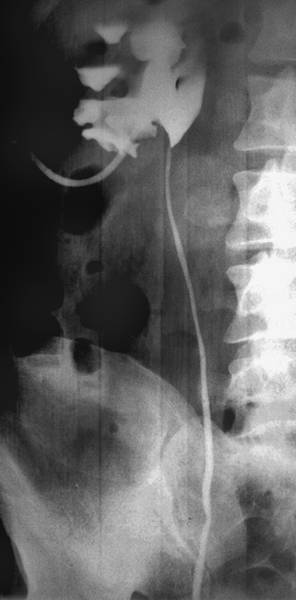

ОБЗОРНЫЙ СНИМОК

Любое рентгенологическое исследование в урологии необходимо начинать с обзорного снимка мочевой системы (рис.).

Обзорный снимок органов мочевой системы.

Интерпретацию обзорного снимка начинают с рассмотрения костного скелета: поясничных и нижних грудных позвонков, рёбер, тазовых костей. Иногда на нём удаётся увидеть тени почек, которые расположены слева между телом XII грудного и II поясничным позвонком, справа — между верхним краем I поясничного позвонка до тела III поясничного позвонка. Следует обращать внимание на их форму, величину и контуры, изменение которых позволяет заподозрить патологический процесс в почках. В норме тень правой почки несколько короче и шире левой. Это связано с разным углом наклона вертикальной оси почек по отношению к позвоночнику. Нужно обратить внимание на степень плотности тени, как по всей её площади, так и в отдельных сегментах. Далее обращают внимание на тень поясничных мышц (m. psoas). В норме она имеет вид усечённой пирамиды, вершина которой расположена на уровне тела XII грудного позвонка. Изменение или исчезновение контуров этой мышцы на одной из сторон наблюдают при воспалительных или опухолевых процессах в забрюшинном пространстве. Отсутствие тени поясничных мышц при травме почки свидетельствует о наличии урогематомы в забрюшинном пространстве.

Мочеточники в норме на обзорном снимке не видны. Иногда, если мочевой пузырь наполнен насыщенной мочой, заметна его тень. В норме на обзорном снимке он имеет форму эллипса.

После оценки естественных структур обращают внимание на наличие добавочных теней. Они различаются по форме, величине, контрастности, однородности. Часто на рентгенограмме видны просветления, обусловленные кишечными газами.